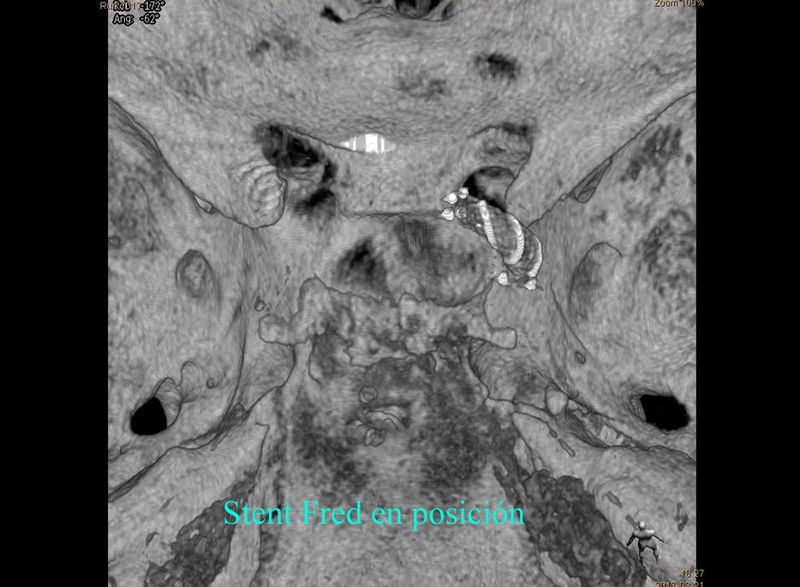

Aneurisma de cara posterior de A1